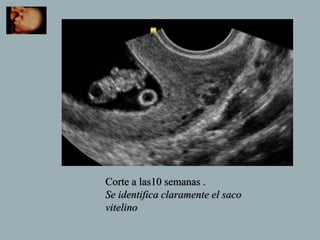

Corte a las10 semanas .

Se identifica claramente el saco

vitelino